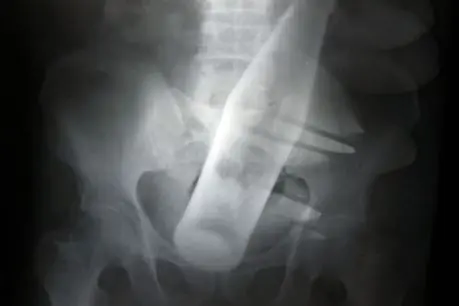

Kenneth Pinyan, de Seattle murió de peritonitis aguda, después de intentar un coito anal con un semental en la ciudad de Enumclaw, Washington. Pinyan había hecho esto antes, y retrasó su visita al hospital por varias horas, dado a la repugnancia luego del conocimiento oficial, el caso condujo a la prohibición del sexo con animales en Washington.